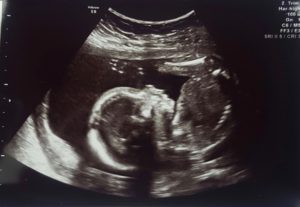

Almost a year after they started trying to conceive, the couple finally found out they were expecting. Sam took five pregnancy tests to confirm the news. “I guess, in a way, the whole ‘it’ll happen as soon as you stop trying’ thing was kind of true. Either that or all we had to do was just talk to a fertility specialist to get pregnant,” she says.